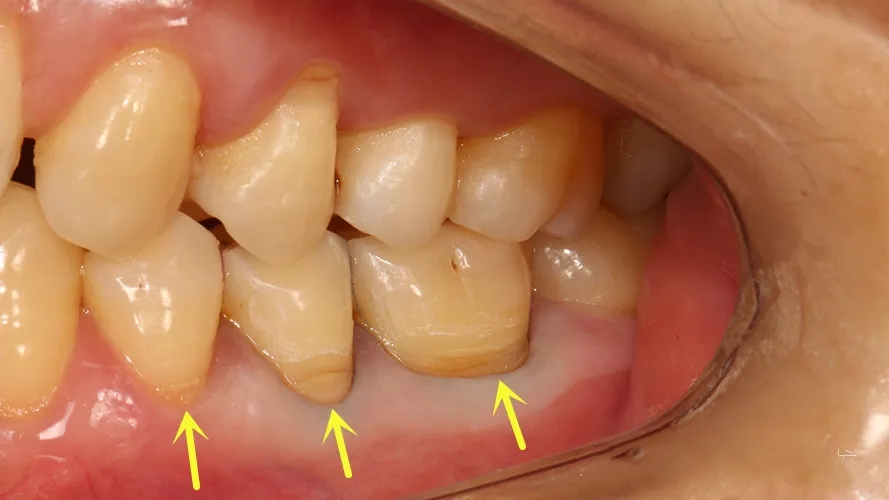

指发生在牙齿唇、颊面颈部的慢性硬组织缺损,呈“V”状,由于它外形酷似木匠用的楔子,因此称为“楔状缺损”。

2、缺损越来越大时,出现敏感甚至自发痛症状,严重者可导致牙齿折断。这经常出现在第一前磨牙,它位于牙弓弧度最突出处。刷牙时受力大、接触次数多,缺损有时还会伴随牙龈退缩。